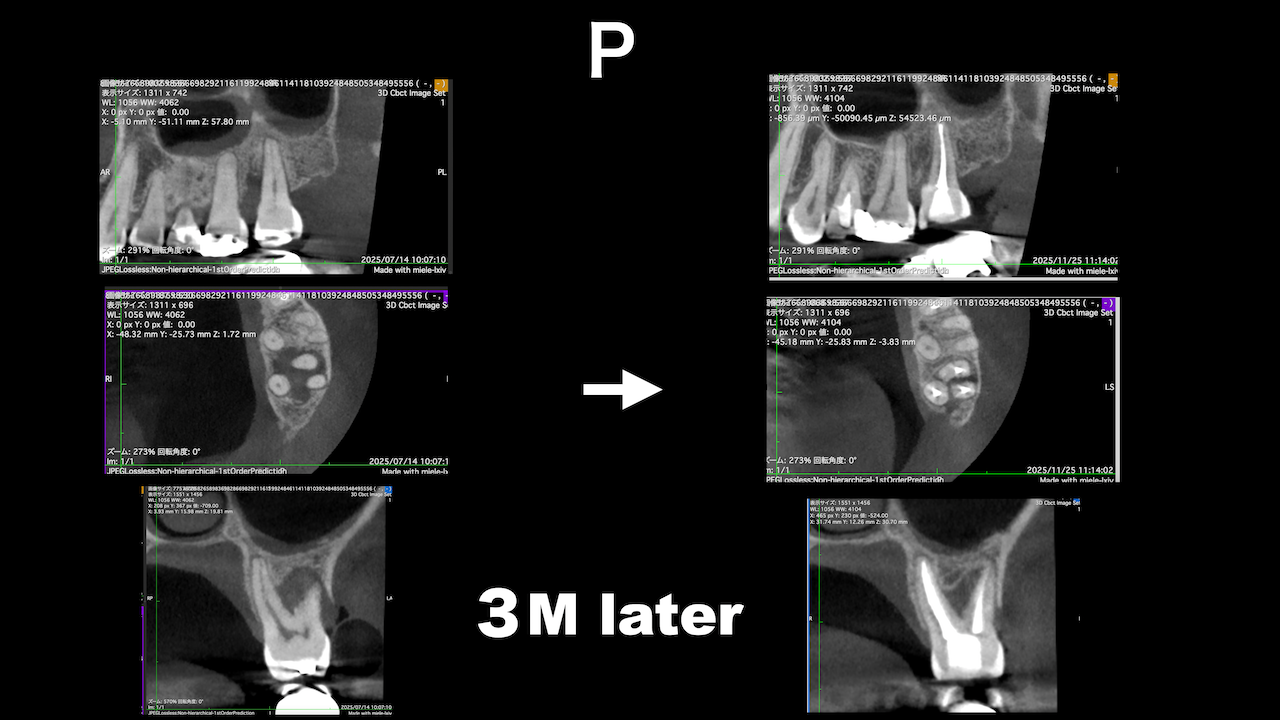

ここから3ヶ月が経過した。

ここから3ヶ月後が以下だ。

3ヶ月で大幅に状況が改善されている。

3ヶ月しか経過していないが根尖病変は大きく減少した。

3ヶ月経過した。

DBの病変が小さくなっている。

Pは病変が大きくなっていうように見えるがまだわからない。